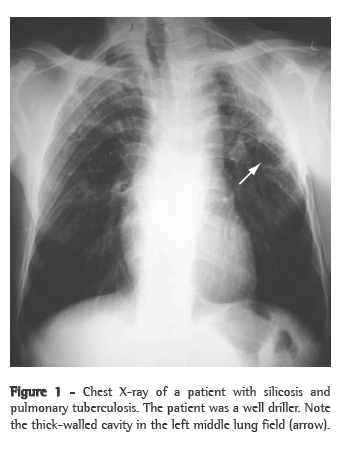

As an initial additional evaluation, it is recommended that sputum smear microscopy and sputum culture (induced sputum culture, if necessary, since it has good sensitivity) be performed, as well as chest X-ray,(23,26) as shown in Figure 1. In cases in which there are still doubts about the presence of active tuberculosis, bronchoscopy with BAL can be used, in conjunction with transbronchial biopsy when possible; biopsies significantly increase the diagnostic yield of the test, even in patients whose sputum and BAL are negative for mycobacteria.(27)

Patterns suggestive of silicotuberculosis have also been recognized on chest CT scans. The principal findings consistent with active tuberculosis superimposed on silicosis are thick-walled cavities (Figure 2), consolidations, images presenting a tree-in-bud pattern, nodular image asymmetry, and rapid disease progression.(26,28,29).